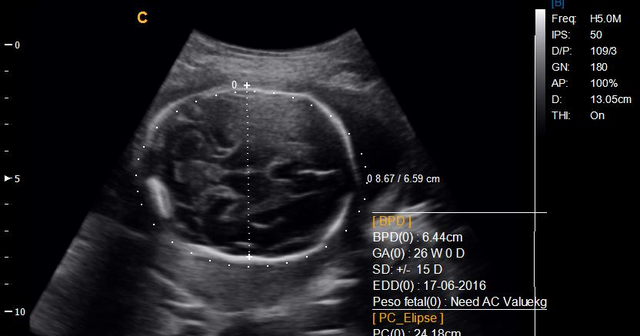

• Se inicia la utilizacion habitual del diagnostico por ultrasonidos

Se inicia la utilizacion habitual del diagnostico por ultrasonidos